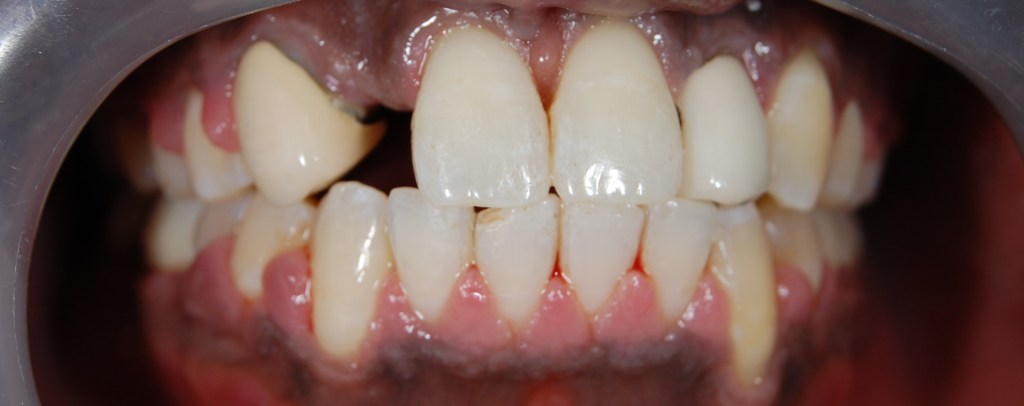

Funkcionális és esztétikai kezelés: harapás korrigálása a fogív kiegyenesítése, fogak közötti rések szűkítése, kereszt harapás megszüntetése az összes megmaradt fog koronázásával. A hiányzó hátsó fogak pótlása implantátumokon megtámasztott koronákkal.

Protetikai munka elkészülésének ideje: 10 munkanap

Koronák anyaga: fémkerámia

Fogszín: A1.